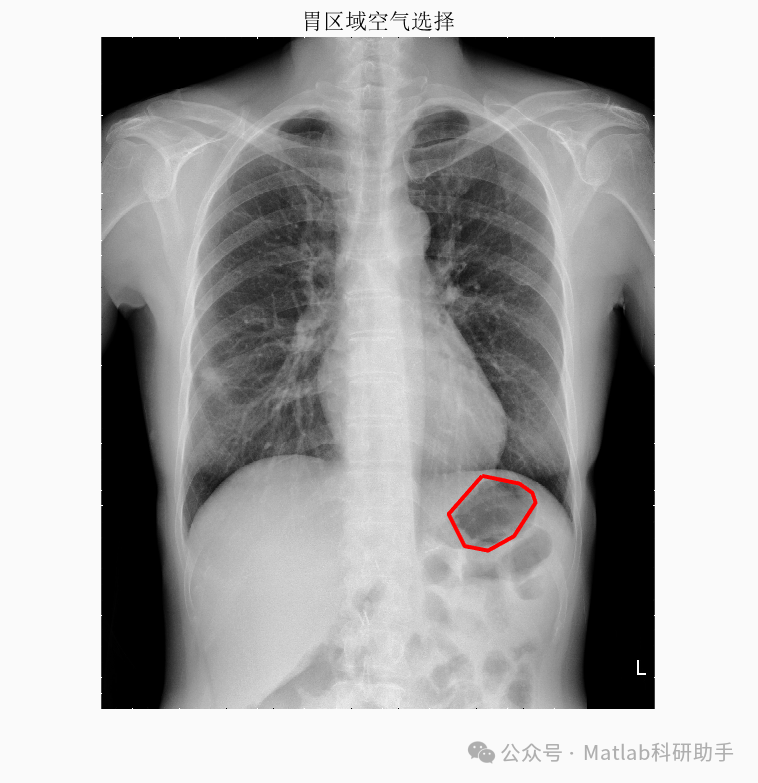

胸片分割作为计算机辅助诊断系统中的关键环节,旨在从胸片图像中精确提取肺部区域,为后续疾病诊断和定量分析提供基础。传统的胸片分割方法往往依赖于人工设计的特征或复杂的图像处理流程,鲁棒性较差。近年来,深度学习凭借其强大的特征学习能力,为胸片分割带来了新的突破。

基于最小误差法的胸片分割系统,通常采用深度学习模型,如U-Net或其变体,作为核心分割引擎。该模型通过大量标注数据进行训练,学习从胸片图像到肺部区域掩膜的映射关系。其核心思想是最小化模型预测的分割结果与真实标注之间的误差,从而实现准确的分割。